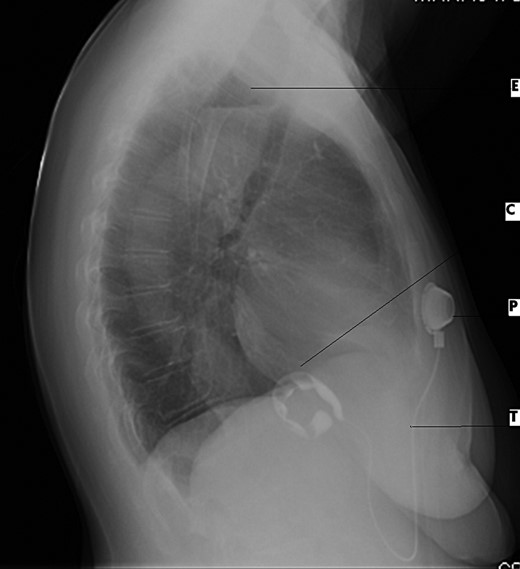

Lateral CXR view demonstrates dilated esophagus and fluid air level (E), contrast medium-filled inflatable inner cuff (C), connecting silicone tube (T) and subcutaneous sutured radiopaque access port (P).